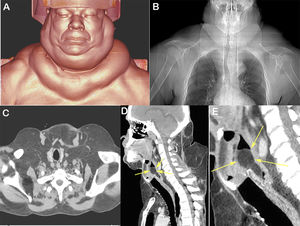

A 62-year-old man presented to the emergency department with severe dyspnea and stridor. He also reported the gradually progressive appearance of masses on his trunk and neck. He had a history of heavy alcohol consumption. Physical examination revealed painless multilobulated tumors of soft elastic consistency in the cervical and shoulder area. Computed tomography of the neck and thorax showed excess fat scattered throughout the neck, upper trunk and superior mediastinum (Fig. 1A–C), and a fatty mass in the larynx affecting the epiglottis (Fig. 1D, E). The final diagnosis was Madelung's disease. Due to the intense dyspnea, tracheotomy was performed and the laryngeal tumor was removed by microlaryngoscopy. Histological examination revealed mature adipose tissue. The patient's postoperative course was uneventful.

In A, chest computed tomography image obtained with three-dimensional coronal reconstruction showing the appearance of the patient's cervical region. In B, computed tomography image of the cervical region demonstrating the abnormal accumulation of lipomatous tissue, scattered particularly in the anterior neck region. In C, computed tomography scout image showing excess fat in the neck and upper trunk. In D, sagittally reconstructed image of the cervical region demonstrating a lipomatous mass in the larynx affecting the epiglottis (arrows). In E, detail of the mass in the larynx (arrows).